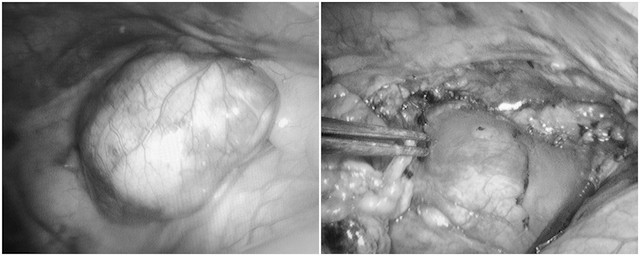

Sau khi gây mê nội khí quản bằng ống Carlens thông khí 1 phổi, các phẫu thuật viên đã sử dụng hệ thống nội soi 3D qua 3 vết rạch nhỏ vào khoang màng phổi phải để thực hiện phẫu tích tỉ mỉ, bóc tách và cắt toàn bộ tuyến ức và tổ chức mỡ ở trung thất trước.

Nhờ camera 3D mang lại hình ảnh phẫu trường chân thực, sắc nét, sau hơn 1 tiếng toàn bộ tổ chức tuyến ức, khối u và tổ chức mô liên kết được lấy bỏ ra khỏi các mạch máu và màng tim mà không bị mất máu.

Bác sĩ CKII Phạm Việt Hùng – Trưởng khoa Ngoại, Bệnh viện Đa khoa tỉnh Quảng Ninh, cho biết: “Khối u tuyến ức của bệnh nhân H. có kích thước khá lớn, nằm ở vị trí nguy hiểm, sát tim, phổi và tiếp xúc với quai động mạch chủ.

Đây là một thách thức đối với đội ngũ phẫu thuật viên, bởi nếu không cẩn trọng, tỉ mỉ thì quá trình bóc tách u có thể tác động đến các cơ quan mạch máu, dây thần kinh và bộ phận quan trọng, gây chảy máu khó cầm, thậm chí tử vong ngay trên bàn mổ.

Với sự hỗ trợ đắc lực của kíp gây mê và hệ thống nội soi 3D, chúng tôi đã bóc tách thành công khối u và toàn bộ tuyến ức ra và đưa ra ngoài mà không gây tổn thương.

Phương pháp này giúp bệnh nhân lấy được triệt để tuyến ức với đường mổ nhỏ ít xâm lấn nhất, giảm đau đớn, hạn chế biến chứng, thời gian hồi phục nhanh và tính thẩm mỹ cao".